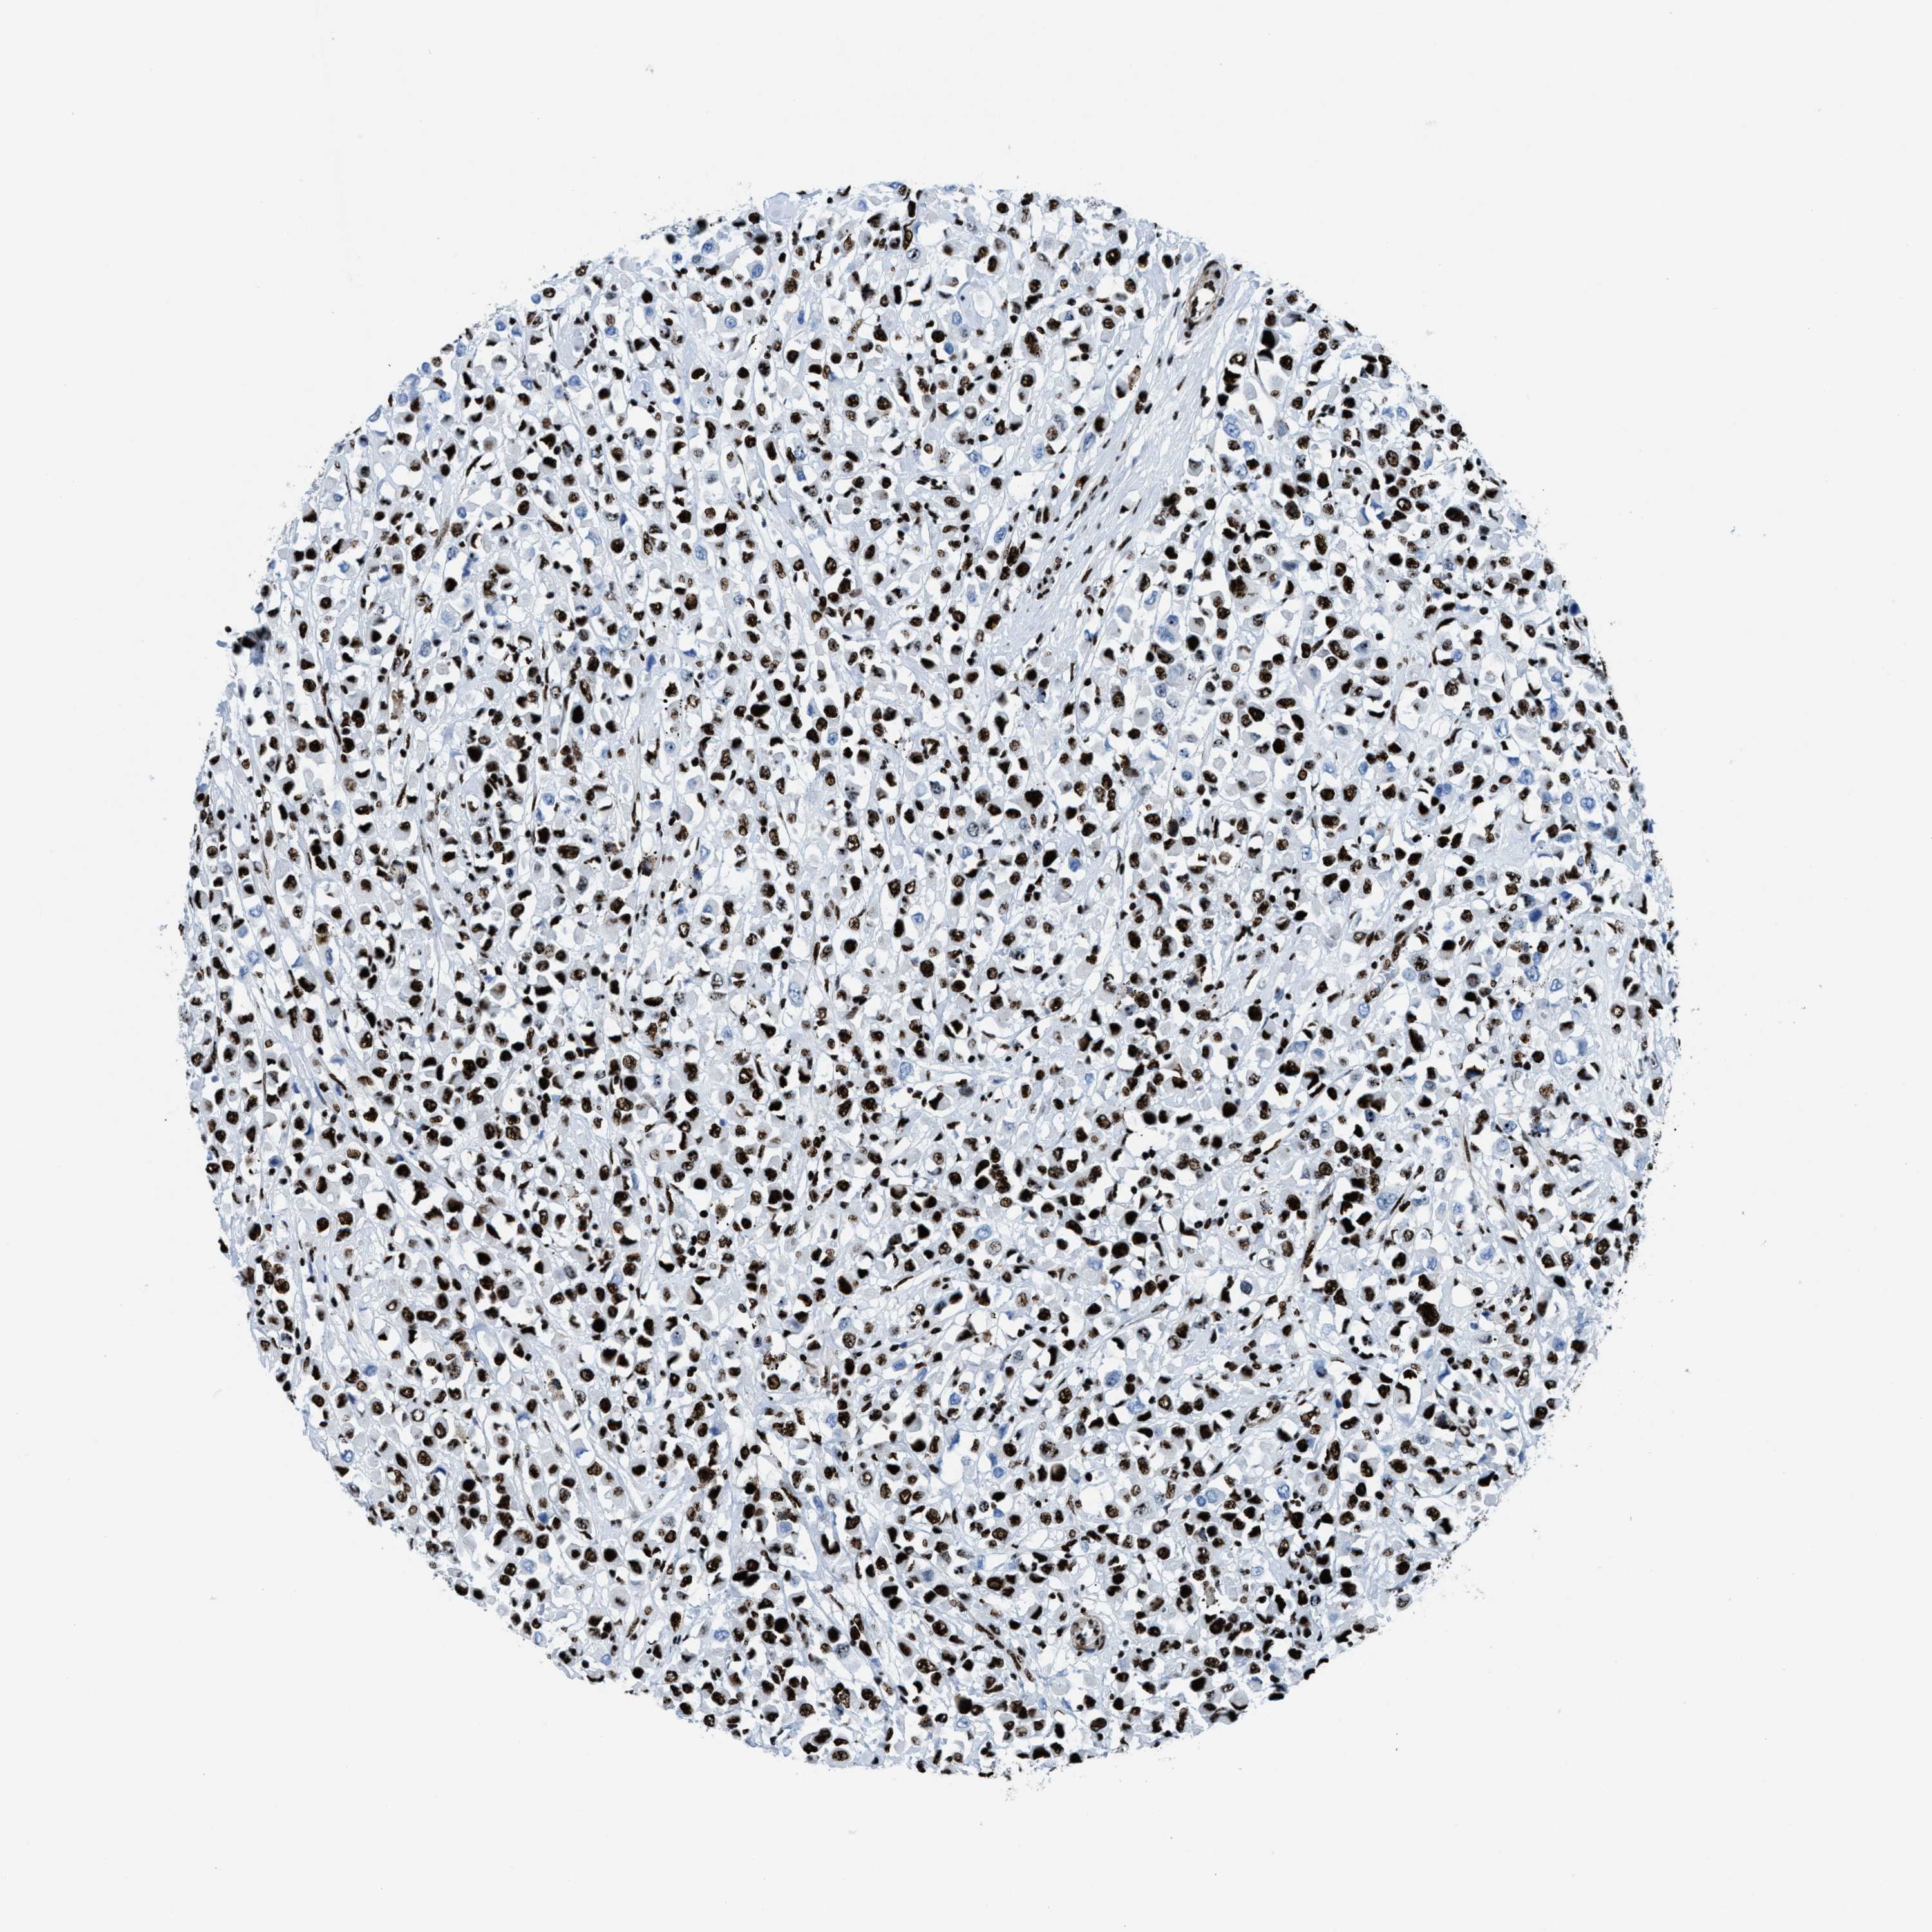

NONO

CANCER BREAST CANCER Show tissue menu

BRCA TCGA BRCA VALIDATION PROTEIN EXPRESSION

Breast cancer

Human cancer

NONO is not prognostic in Breast Invasive Carcinoma (TCGA)